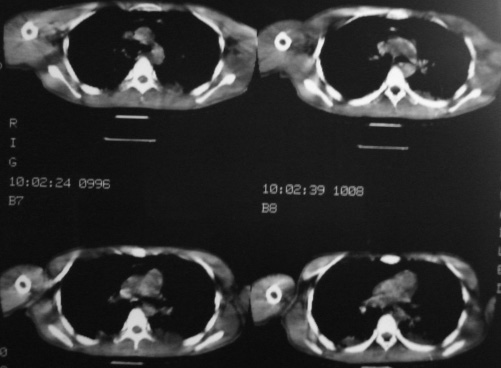

男,18岁,车祸20小时后胸ct.血氧饱和度80,呼吸45次/分.

2:纵隔气肿。

1:两侧创伤性湿肺。

两肺挫伤,纵隔气肿,两侧气胸

1:两侧创伤性湿肺(撕裂伤)。

2:纵隔气肿.